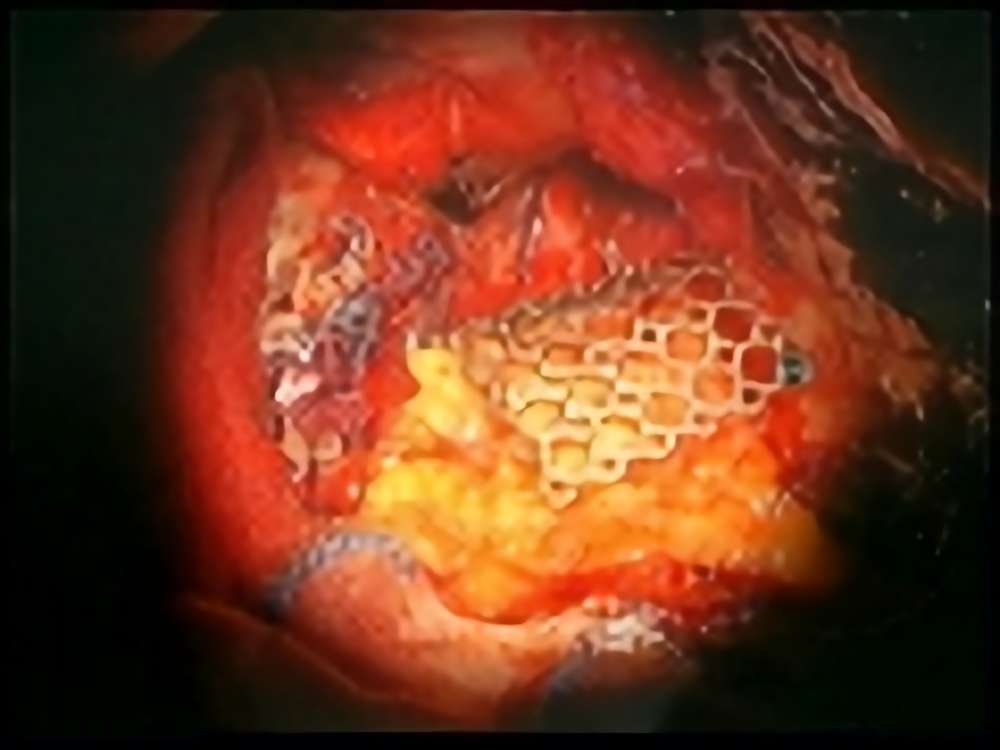

No.’15_13 摘出 前

No.’15_13 摘出 後